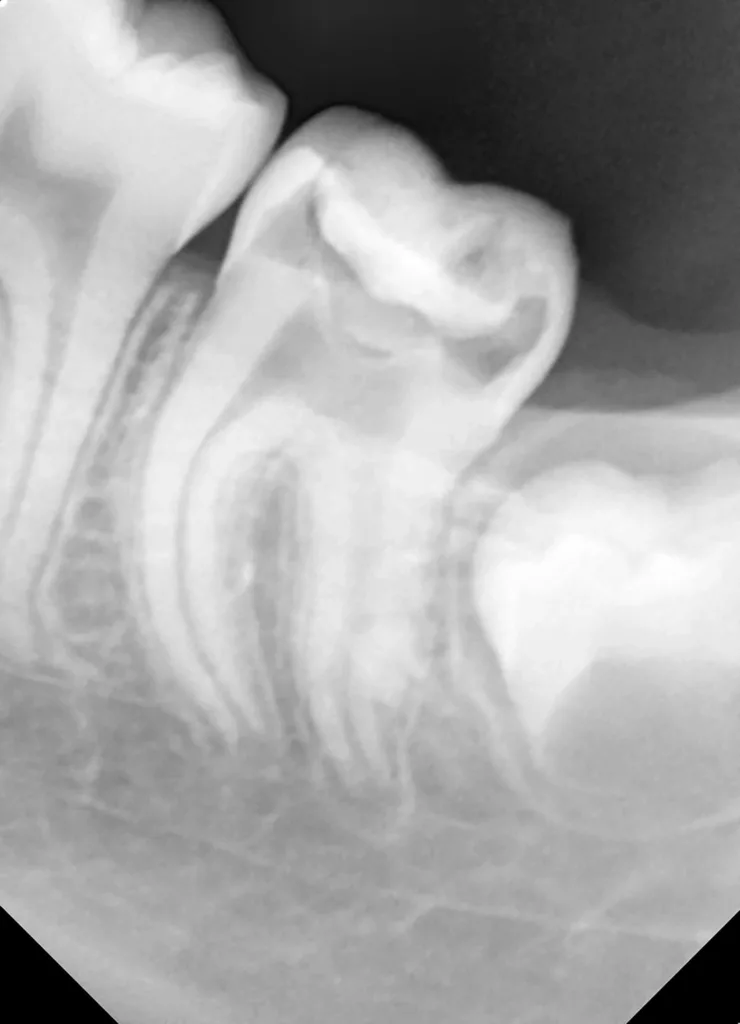

Bei routinemäßigen Röntgenkontrollen ergeben sich manchmal Zufallsbefunde unklarer Genese. So stellt sich beispielsweise bei der Betrachtung der Abbildung 1 die Frage, wie sich ein Zahnhartsubstanzdefekt so schnell entwickeln konnte. Ein weiteres Röntgenbild (Abb. 2), das vor dem Zahndurchbruch aufgenommen wurde, zeigt jedoch, dass es sich in diesem Fall nicht um Karies, sondern um die sogenannte präeruptive intrakoronale Resorption (PEIR) handelt. Für diesen Befund finden sich in der Fachliteratur auch noch andere Bezeichnungen wie „idiopathic external resorption of unerupted permanent teeth“ [1], „intra-follicular caries“ [2], „radiolucent lesions resembling caries“ [3], „occult caries“ [ 4] oder „pre-eruptive caries“ [5].

V. Slabkovskyi, O. Liutikovwährend des Durchbruchs des Zahnes 36.

Das fünfjährige Mädchen stellte sich 2017 zur jährlichen Routinekontrolle vor. Im Rahmen der Untersuchung wurden Röntgenaufnahmen der Milchmolaren gemacht (Abb. 2). Der klinische und radiologische Befund der vor uns früher gelegten Kompositfüllungen war gut, es wurde allerdings eine PEIR an den noch nicht durchgebrochenen ersten bleibenden Molaren festgestellt (Abb. 2). Den Eltern wurde empfohlen, sich unverzüglich bei Beginn des Durchbruchs der ersten Molaren erneut zur Behandlung vorzustellen. Ein Jahr später erschien die junge Patientin schmerzfrei zur Kontrolle. Der Zahn 36 war noch teilweise mit Gingiva bedeckt. Auf einer neuen Röntgenaufnahme (Abb. 1) wurde die PEIR-Läsion mit unveränderter Größe in pulpanahen Bereichen bestätigt (Grad 3 der Läsion nach Seow). Der Zahnschmelz sah intakt aus, es konnte kein pathologischer periapikaler Befund bei den noch nicht ausgewachsenen Zahnwurzeln festgestellt werden. Daraufhin wurden die verschiedenen Behandlungsmöglichkeiten von Fissurenversiegelung bis Vitalerhaltung der Zahnpulpa mit den Eltern des Kindes besprochen.